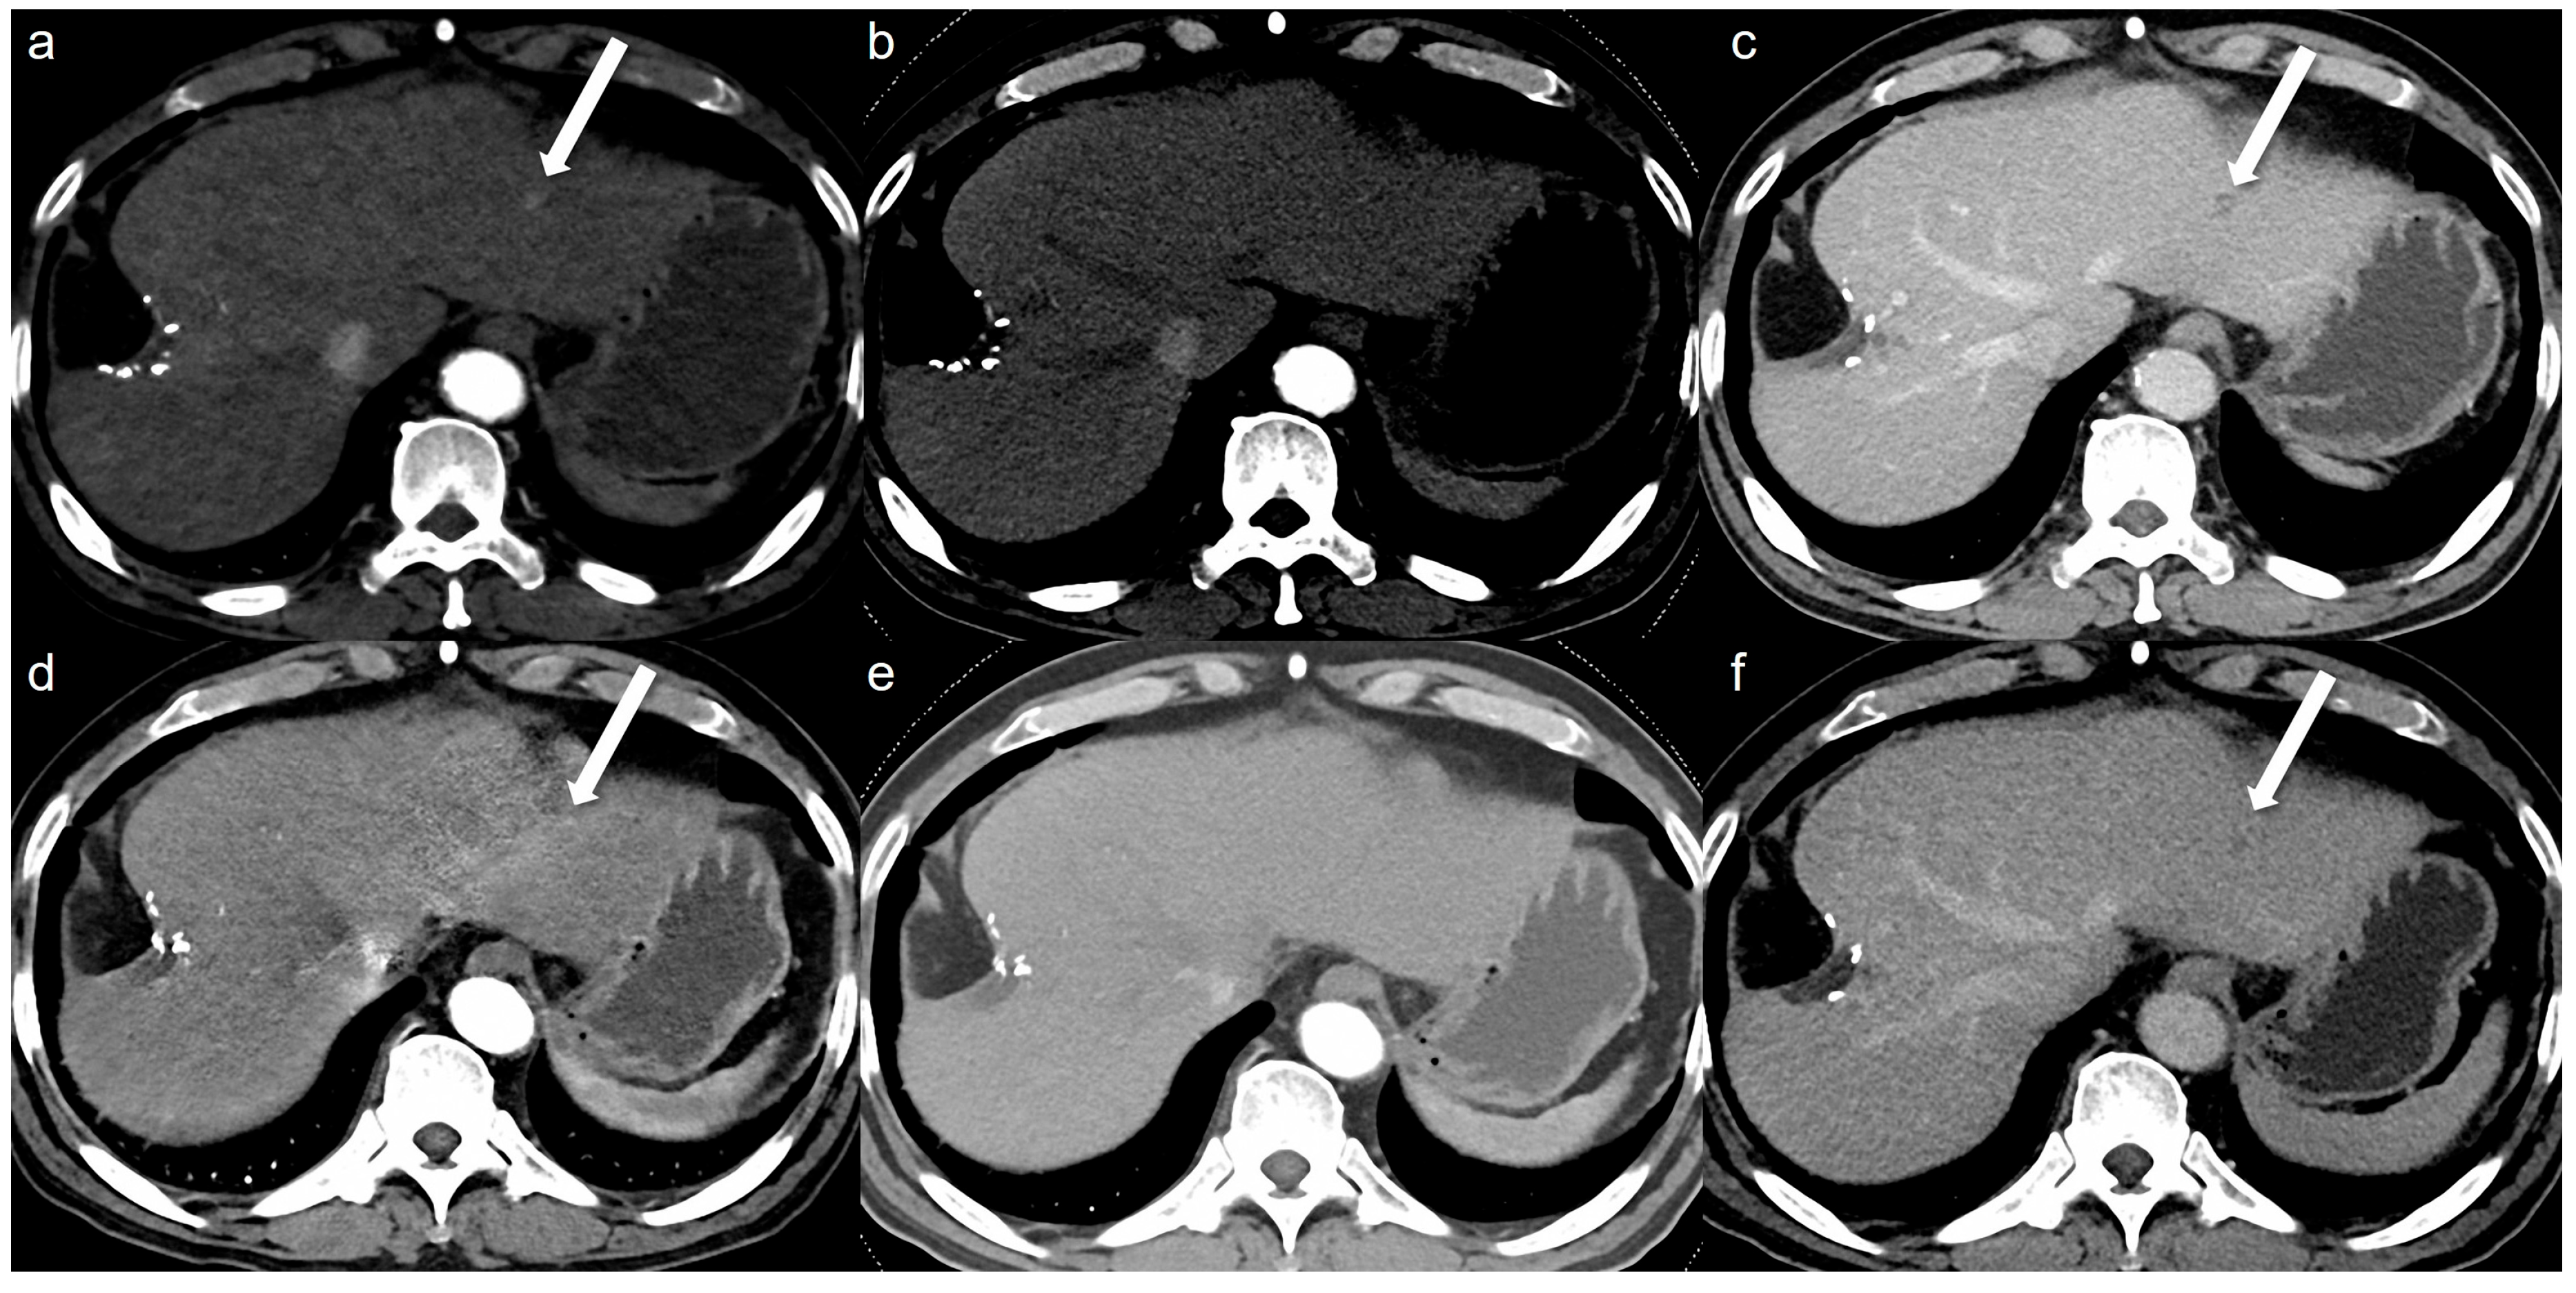

Figure 2.

A 64-year-old man with hepatocellular carcinoma (HCC). Although the HCC was not detected by either reviewer on both the low-concentration iodine contrast-enhanced low-monoenergetic CT and the standard-dose CT, retrospective evaluation reveals the presence of an arterial enhancing lesion. Low-concentration iodine contrast using a low-monoenergetic CT and standard-dose CT were performed with a 3-month interval. In the low-concentration contrast medium (270 mg I/mL) monoenergetic 40 keV image (a), subtle arterial enhancement measuring approximately 9 mm is visible (arrow). However, arterial enhancement is not observed in the blended image (b) (a mixed ratio of 0.5, 50% 100 kV and 50% Sn140 kV). The portal phase image (c) reveals the washout (arrow). The standard-dose CT with 350 mg I/mL also showed subtle arterial enhancement in the monoenergetic image (d, arrow), which was not visible in the blended image (e) (a mixed ratio of 0.5, 50% 100 kV and 50% Sn140 kV) even though the portal phase washout was clearly seen (f, arrow). This lesion was confirmed as HCC on MRI with gadoxetic acid. This case illustrates that although low-monoenergetic CT images are associated with higher noise, the improved contrast-to-noise ratio can facilitate the detection of subtle arterial enhancing lesions.